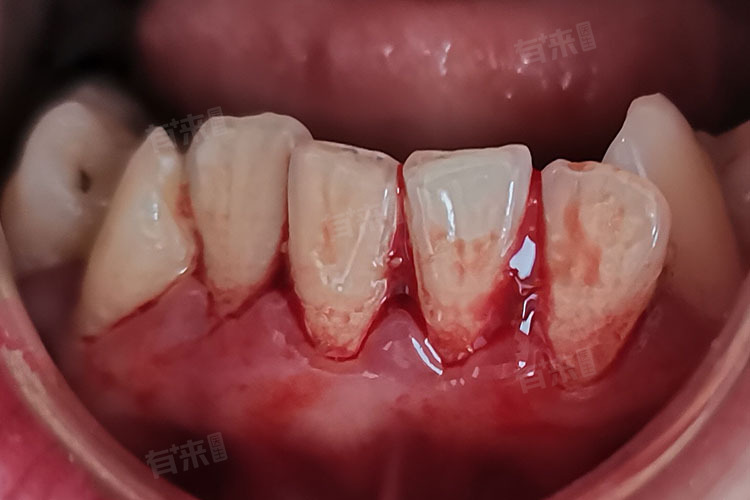

- 牙龈炎:牙菌斑和牙结石的长期堆积,会刺激牙龈,引发牙龈炎,牙龈炎的主要症状之一就是牙龈出血,尤其在刷牙或咬硬物时更为明显,患者的牙龈通常会呈现红肿状态,质地松软。

- 牙周炎:是一种更为严重的牙周疾病,不仅涉及牙龈,还影响到牙周膜、牙槽骨等牙周组织,炎症会导致牙龈退缩、牙周袋形成,容易引起出血,而且出血往往较为频繁,还可能伴有口臭、牙齿松动等症状。